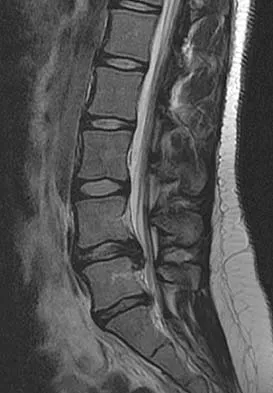

A 50-year-old man with no history of trauma reports new-onset back pain after doing some yard work the previous day. He reports pain radiating down his leg posteriorly and into the first dorsal web space of his foot. MRI scans are shown in Figures 3a through 3c. What nerve root is affected?

The MRI scans clearly show an extruded L4-5 disk that is affecting the L5 nerve root on the left side. In addition, the L5 nerve root has a cutaneous distribution in the first dorsal web space. S1 affects the lateral foot. L4 affects the medial calf.